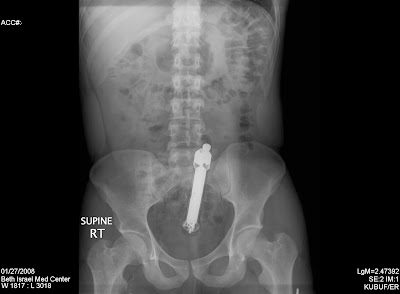

Finally, I leave you with a gift. These are the kinds of things I went into medicine for. Although surgery rotation sucked, it was all worth it when we took an X-ray of a male patient to find this:

Yes, it's a vibrator. You can easily see the inner workings, motor, etc. but it may be hard to see the outer casing so I ever-so-precisely outlined it in red, below:

So the moral of the story, boys and girls, is have your fun but be careful: stick something far enough up your ass, and it may not cum back out....without surgery...& the surgical team laughing at you...and a 3rd-year med student posting it on the internet.